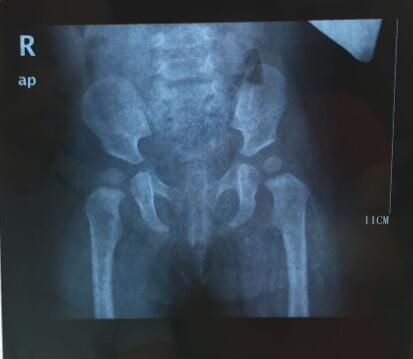

求助大神,帮我看看,我感觉有点不对啊

髋关节脱位吧